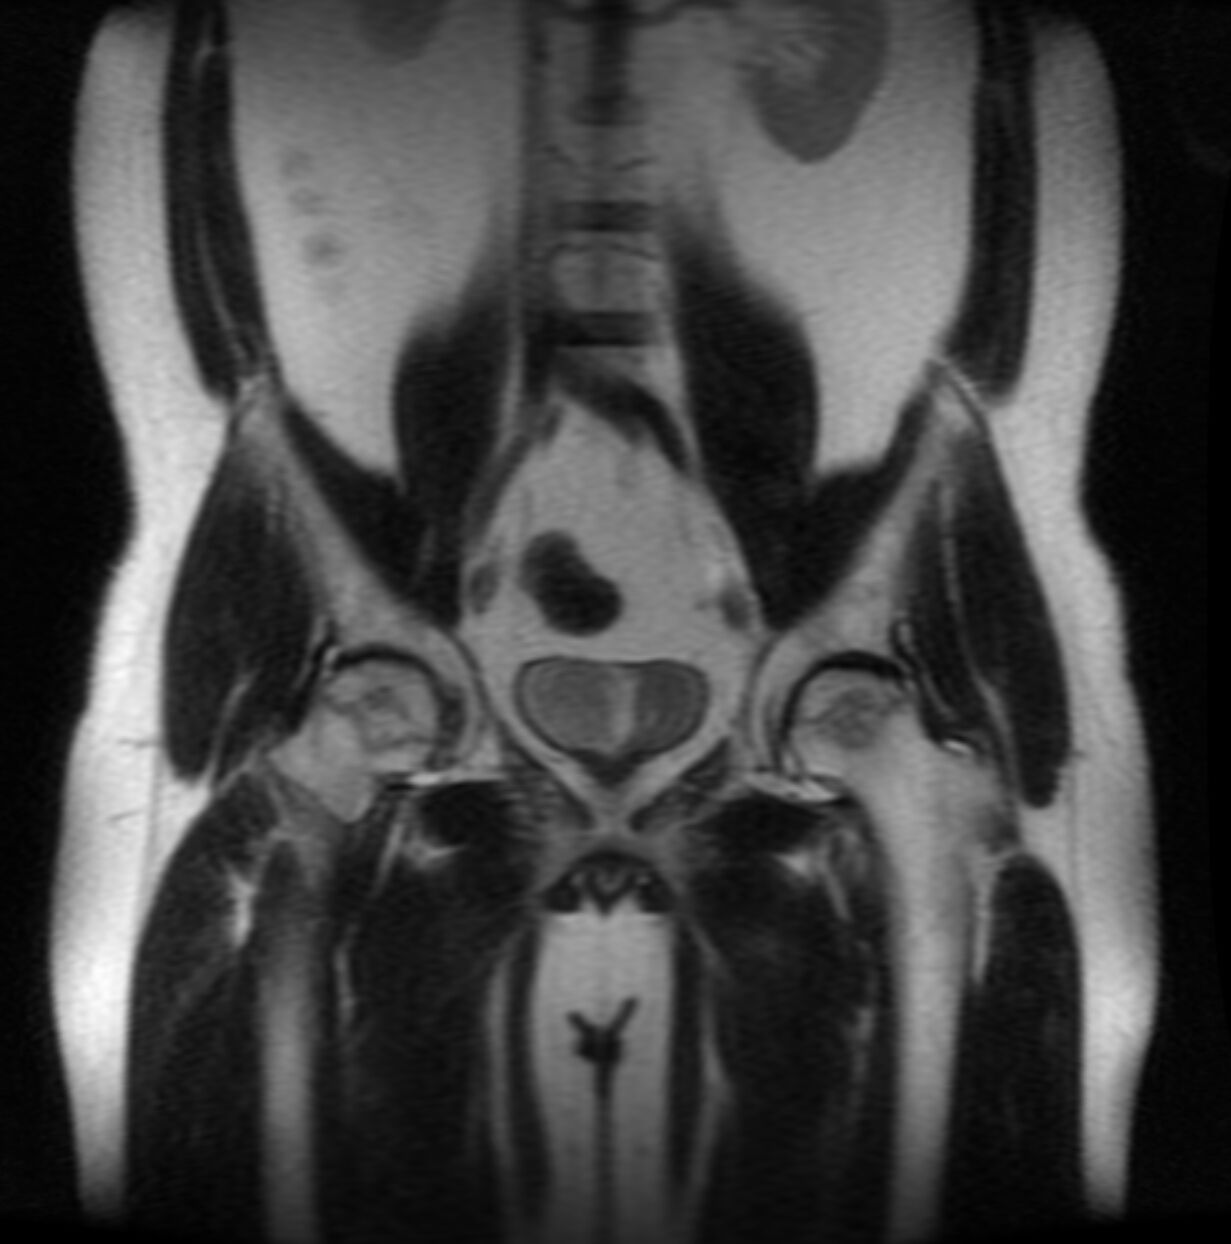

Felhívnám a figyelmeteket a TDP-re és az alatta lévő hőfokra:

Ez egy 13900HX ami 130W-on stabilan ketyeg 4GHz-en allcore és

70-75 fokos közben. Ezt tudja az 1500W/mK-es grafén lap

A gép a 2023-as Lenovo Legion, hőcsöves hűtéssel! -